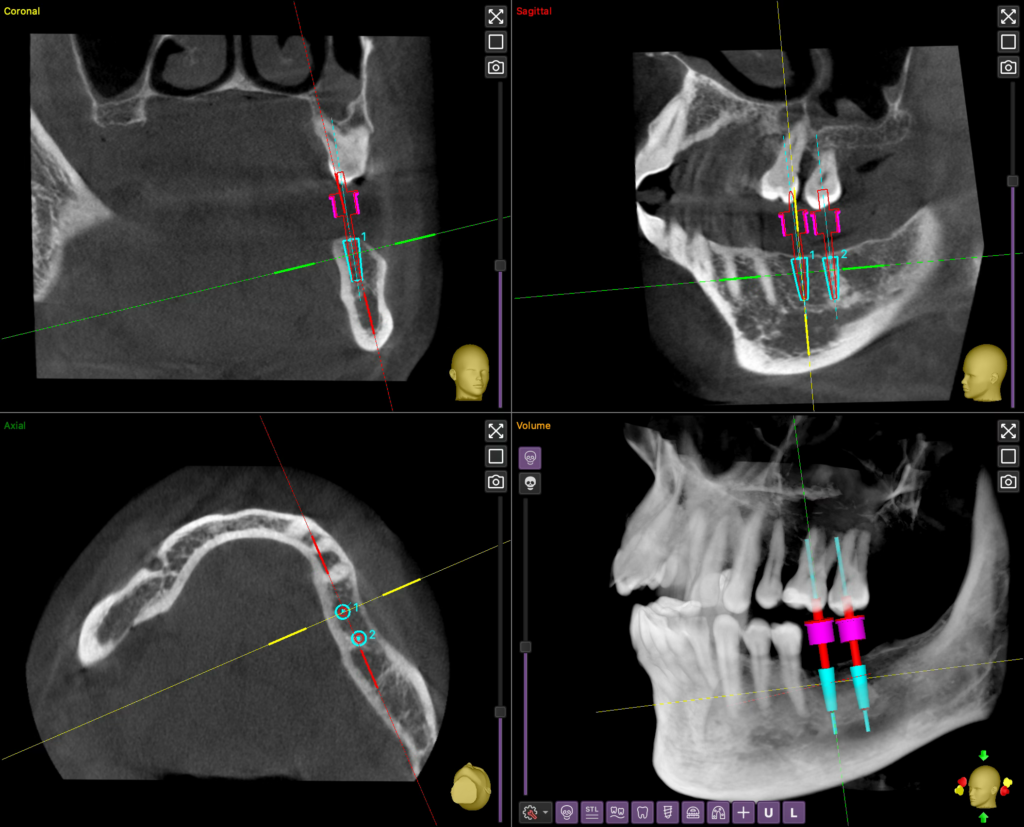

A CBCT: A Fogászati 3D Képalkotás

A CBCT (Cone Beam Computed Tomography) egy speciális, modern 3D képalkotás a fogászatban, mely sokkal több információt nyújt, mint a hagyományos, 2D röntgenfelvételek.

A hagyományos felvételekkel ellentétben, amelyek elfedhetik az elváltozásokat, a CBCT-vel az  orvos minden szögből, torzításmentesen láthatja a fogakat, állcsontokat és az arcüreget.

Ez a pontos 3D nézet elengedhetetlen a beültetendő implantátumok tervezéséhez, mivel segít meghatározni az ideális helyet, elkerülve a fontos idegeket és ereket.

Használata fontos lehet bonyolultabb gyökérkezelések előtt is, mivel kimutatja azokat a rejtett, plusz gyökércsatornákat, melyek gyulladást okozhatnak.

Sokat segít azokban az esetekben is, ha a fogfájás oka nehezen beazonosítható, vagy gyanú merül fel egy cisztára vagy daganatra az állcsontban.

Bölcsességfogak eltávolításakor különösen fontos, hogy láthatóvá váljon a fog és az állcsontban futó ideg (idegcsatorna) pontos távolsága.

A képalkotás során alacsonyabb a sugárterhelés, mint egy kórházi CT-vizsgálatnál.

A CBCT-vel kapott adatok biztosítják az orvos számára a legnagyobb kezelési biztonságot és pontosságot.

A CBCT tehát nem egy rutinvizsgálat, hanem egy célzott, tervezési eszköz, melyet akkor kérnek, ha a biztonságos és sikeres végeredmény megköveteli a 3D-s látásmódot.